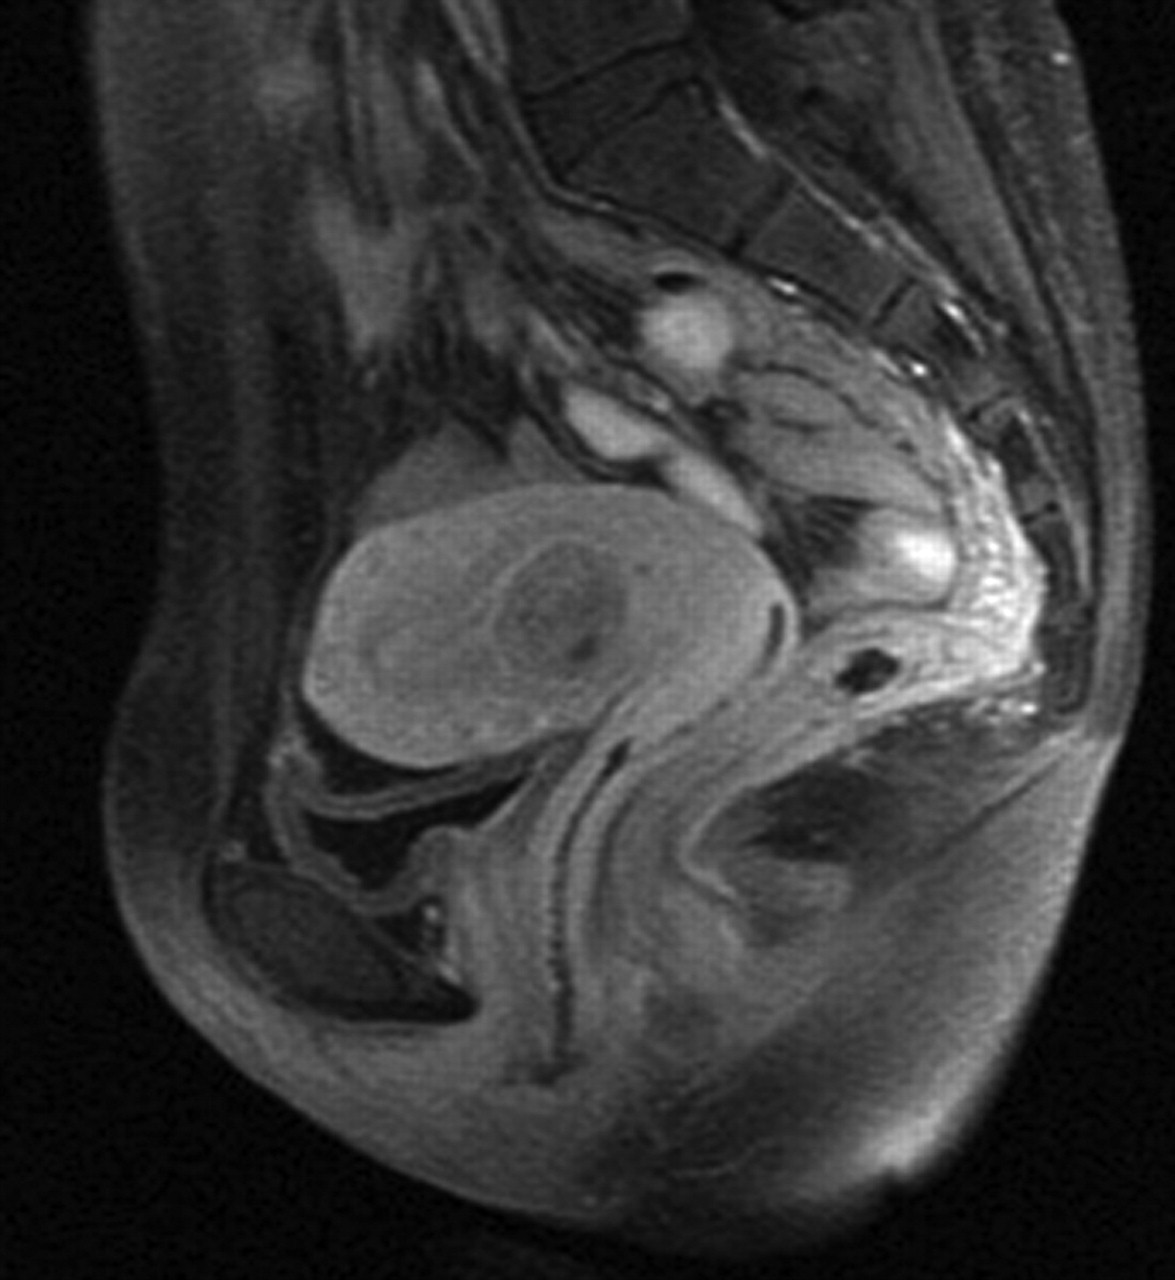

Observe the below images. The first is from an unknown woman, the second is from Maya. The first scan has a growth in the womb, but this is not of importance to this comparison.

Illustration

2: MRI image from unknown woman. Growth visible in womb, but no

effect on other organs.

3: MRI image made of Maya during scan at the Erasmus MC.

To further clarify, another scan of Maya, but this time with the suspected vagina marked:

4: Location suspected vagina of Maya marked. From German scan.

What's clear from this scan is that in all cases the vagina is clearly visible, and the orientation and position match. There are to our knowledge no other organs or structure for either men or women which would give a similar image.